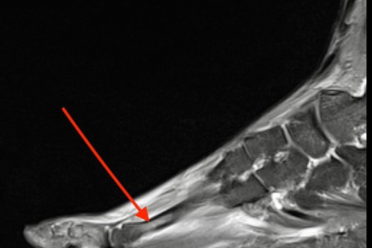

Czy kontuzja Roberta Lewandowskiego da się wyleczyć przed EURO? Kontuzje mięśniowe – naciągnięcia, naderwania i zerwania